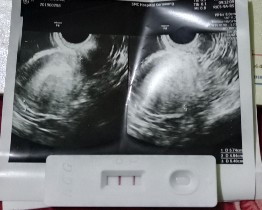

#bantujawab bunda ada yang ngalamin hal sama seperti saya gak bun, saya terakhir mens tgl 14oktober di tgl 22november saya tespek karna telat haid dan hasil nya positif. Dengan bahagia nya saya langsung USG tgl 25november namun pada saat saya USG kata dokter belum terlihat kantung janinnya hanya penebalan dinding rahim dan disarankan untuk balik lg satu minggu kemudian, hari ini tgl 02desember saya barusan USG lg kontrol bahkan saya melakukan USG Transvaginal namun hasil masih tetap sama belum terlihat kantung dan janinnya. Apakah ini hal yang wajar bund?? Saya jadi overthinking bund 🥲 karna 2018 saya pernah mengalami keguguran dgn pendarahan yg hebat pada saat itu. Saya cemas dan takut bun.. Apa karna usia kehamilan saya yg masih muda atau bagaimana ya bund.. #Sharing_dong_Bund Penantian saya sangat lama 7tahun pernikahan 😭 sekalinya positif hamil saya malah dibuat overthinking , #bagi_sarannya_bunda saya jadi cemas , khawatir dan bingung 😢

Assalamualaikum bund, izin sharing semuanya #Sharing_dong_Bund Saya kan positif garis dua, setelah ke bidan dinyatakan usia kandungan saya 6w kurang 2hari, barusan saya ke dokter kandungan begitu usg namun blm terlihat bakal janin nya hanya terlihat penebalan dinding rahim. Kira2 usia minggu ke brp bunda2 yg pengalaman sudah usg dan terlihat jelas bakal janin nya bund?? Jd overthinking saya bund 🥲